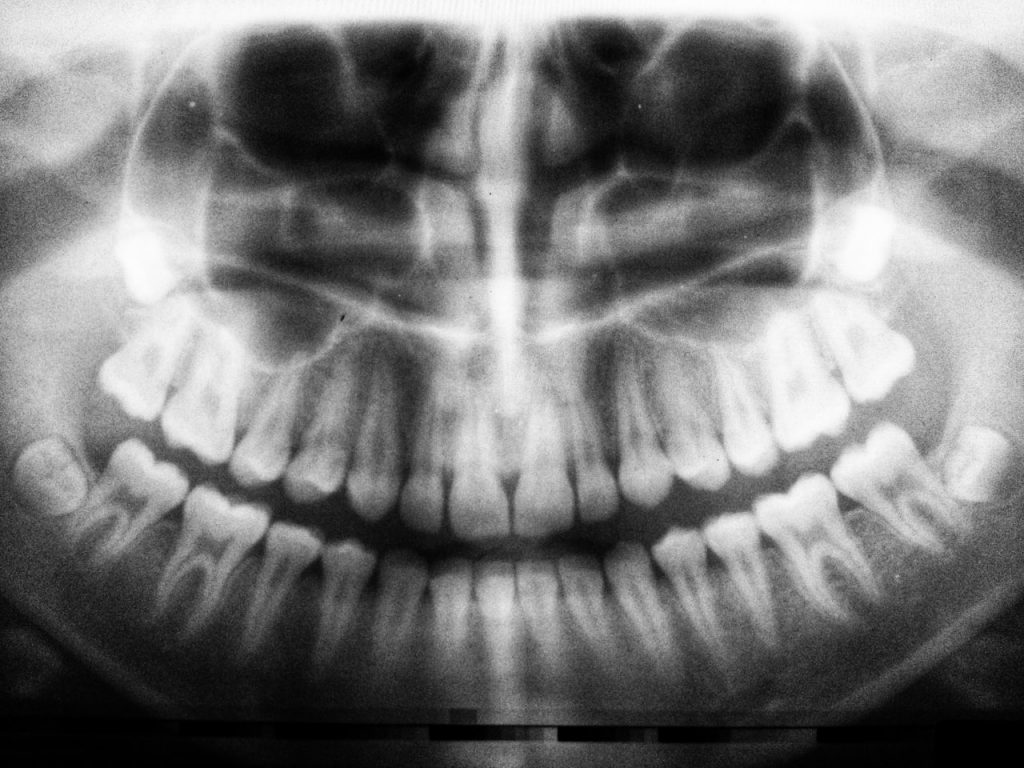

Prima dell’intervento si sviluppa una fase che richiede tempo, attenzione e continuità: raccogliere le informazioni, ricostruire la storia clinica, valutare i tessuti, osservare la funzione masticatoria, integrare eventuali esami radiografici.

Controlli periodici, sedute di igiene orale, monitoraggi clinici e radiografici permettono di mantenere l’equilibrio raggiunto e intervenire quando necessario.

Prima di iniziare una terapia vengono raccolti dati clinici attraverso anamnesi, esame obiettivo, valutazione della funzione ed eventuali esami radiografici. Queste informazioni permettono di formulare una diagnosi e pianificare il trattamento.